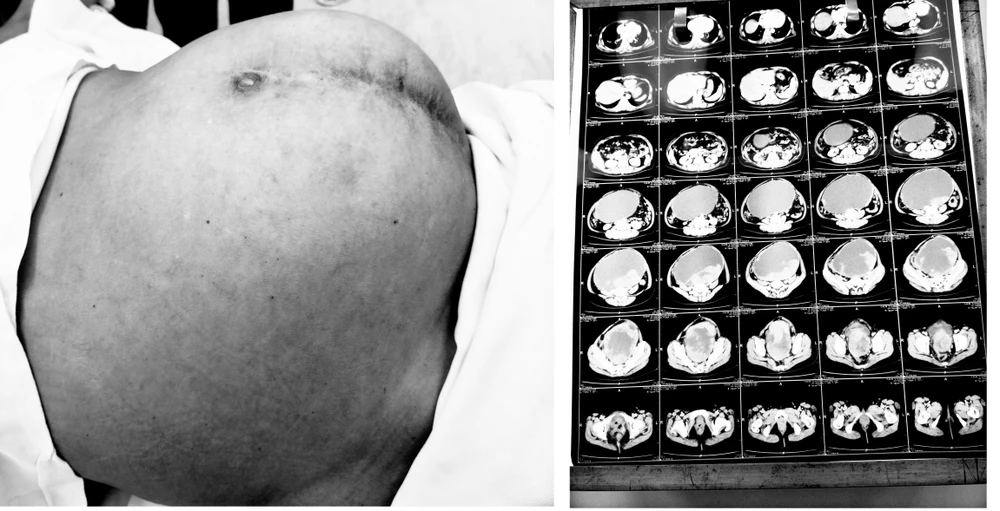

Bụng của bệnh nhân to bất thường lúc nhập viện và kết quả chụp hình ảnh cho thấy khối u rất lớn. Ảnh: BVCC

Qua thăm khám, ban đầu bác sĩ ghi nhận bụng bệnh nhân to như phụ nữ mang thai 6 tháng, sờ có khối u kích thước khoảng 20 x 20 cm ở vùng hạ vị và hố chậu trái, mật độ mềm, không di động, không đau.

Sau khi hội chẩn, các bác sĩ quyết định phẫu thuật lấy khối u cho bệnh nhân. Khi mổ, khối u có kích thước lớn (khoảng 40 x 40 x 30 cm) dính chặt vào các cơ quan xung quanh nên gặp nhiều khó khăn.